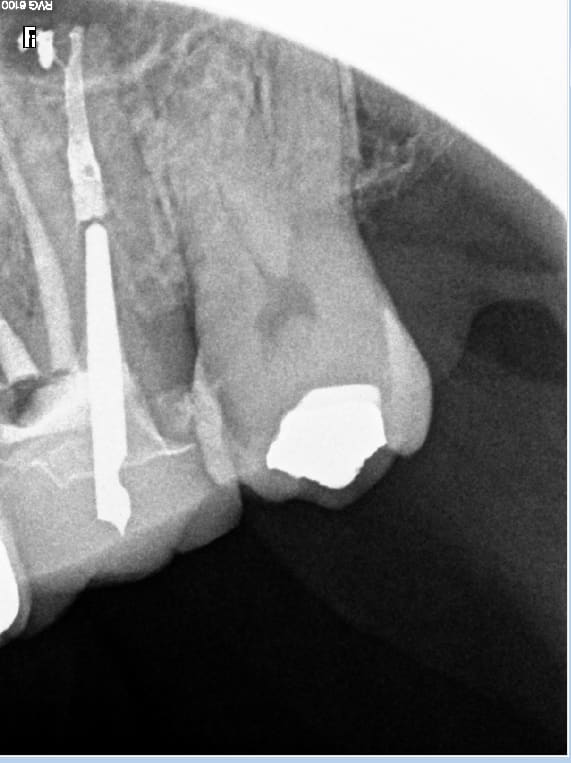

Alors cet enfoiré m'a envoyé la radio.....

Et je lui ai dit : de quoi te mêles tu le patient ne sent rien. -)))

C'était moi le patient. je suis un patient cool. Je n'ai pas voulu mettre mon confrère dans l'embarras. J'ai quand meme été sceptique c'est pour ça que je lui ai demandé de m'adresser la radio de fin de traitement.... Qui ne correspond pas du tout à la radio 7 ans après. Comme quoi éviter de tirer des conclusions hâtives.

Mai 2016. Tiens ? vous avez une lésion à l'apex de 25. J'ai pas mal on laisse. Septembre 2016 débarque en urgence RTE.... octobre 2016 pose ic provisoire. Mai 2019 pose de la définitive. Toi aussi tu lis les posts en diagonale et tu te prends le melon ? -)))

j'adresse pour une 46 symptomatique, et le confrère qui n'est pas endo exclusif fait le job, et détecte pour une raison que j'ignore encore des "kystes" sur 24.25. J'ai réalisé sur ces dents un traitement initial sur 24 et un rte sur 25 avec 2 cr en 2013.

Suite à appel du patient, je comprends que les dents sont a priori asymptomatiques, il me parle de traitements qui ne vont pas au bout des racines et d'un instrument fracturé. Il a un devis rte et prothèse et me demande son dossier, souhaite que je prenne en charge tous les frais, ce que je refuse. Je lui ai dit de me faire un courrier il veut absolument faire jouer mon assurance car pour lui j'ai fait des erreurs.